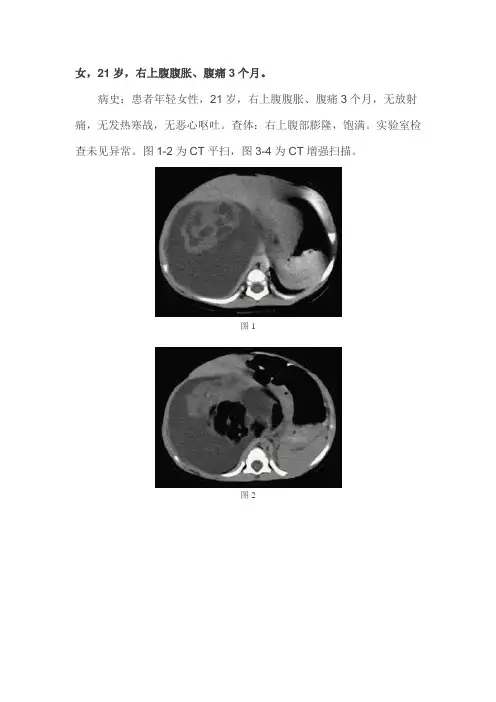

女,21岁,右上腹腹胀、腹痛3个月。

病史:患者年轻女性,21岁,右上腹腹胀、腹痛3个月,无放射痛,无发热寒战,无恶心呕吐。

查体:右上腹部膨隆,饱满。

实验室检查未见异常。

图1-2为CT平扫,图3-4为CT增强扫描。

图1图2图3图4CT影像表现:CT平扫肝右叶可见一巨大的肿块影,边缘光滑,密度不均,其内可见钙化或骨骼、脂肪及液化坏死影;周围组织受压移位。

CT增强扫描显示肿瘤软组织成分不均匀强化。